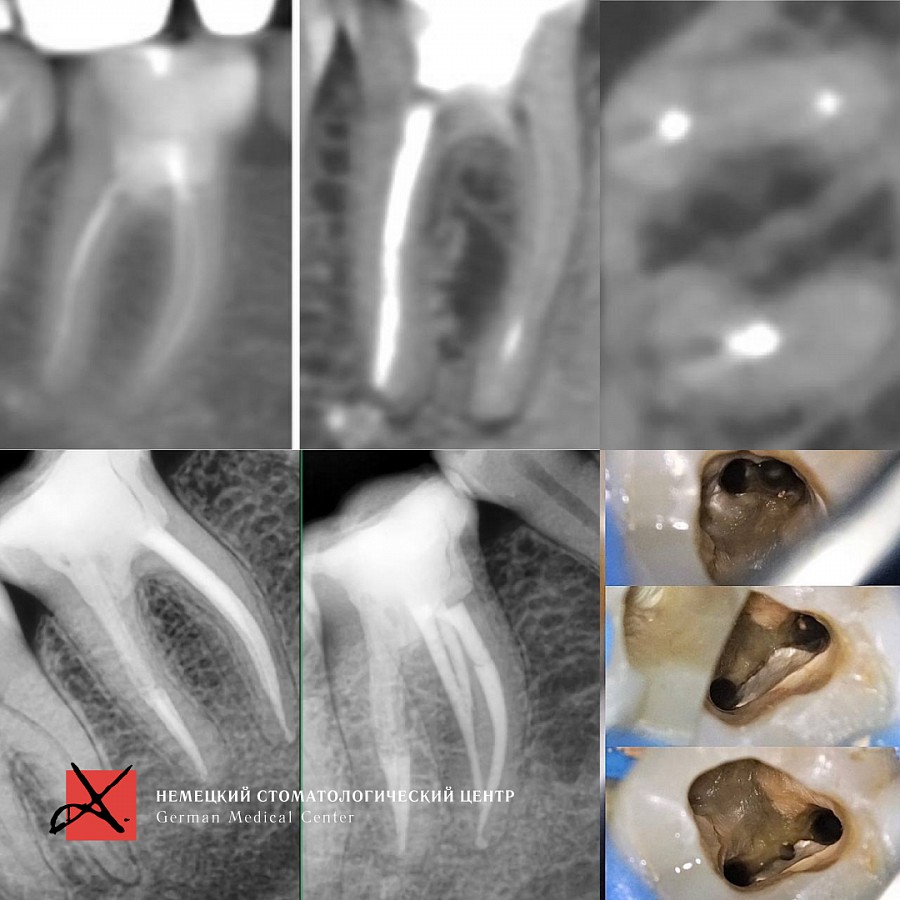

Лечение каналов под микроскопом

Результат лечения